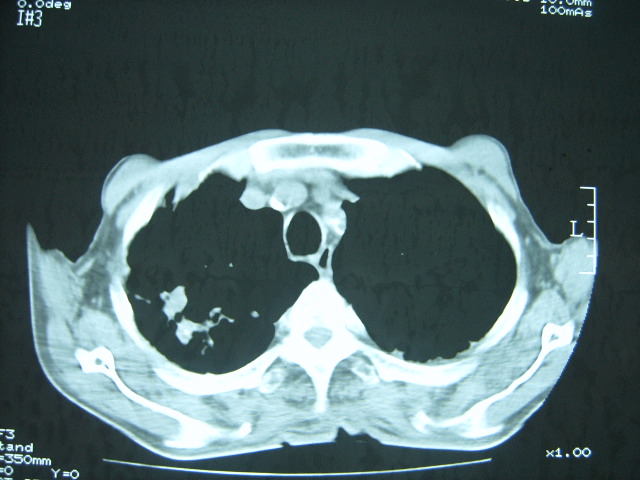

男74岁,咳嗽,寒战,低烧。有糖尿病史。

考虑:糖尿病合并:1、左下肺炎继发肺脓肿;

2、双肺结核。

1、左下肺肺脓肿,合并霉菌球形成?.2、双肺陈旧性病灶.3、右上肺病灶警惕瘢痕癌,建议定期复查.

两肺结核,左下肺大片实变,内见空洞性病变,壁不规则,结合糖尿病史,考虑:结核性?霉菌性?建议结合实验室检查或治疗后复查。